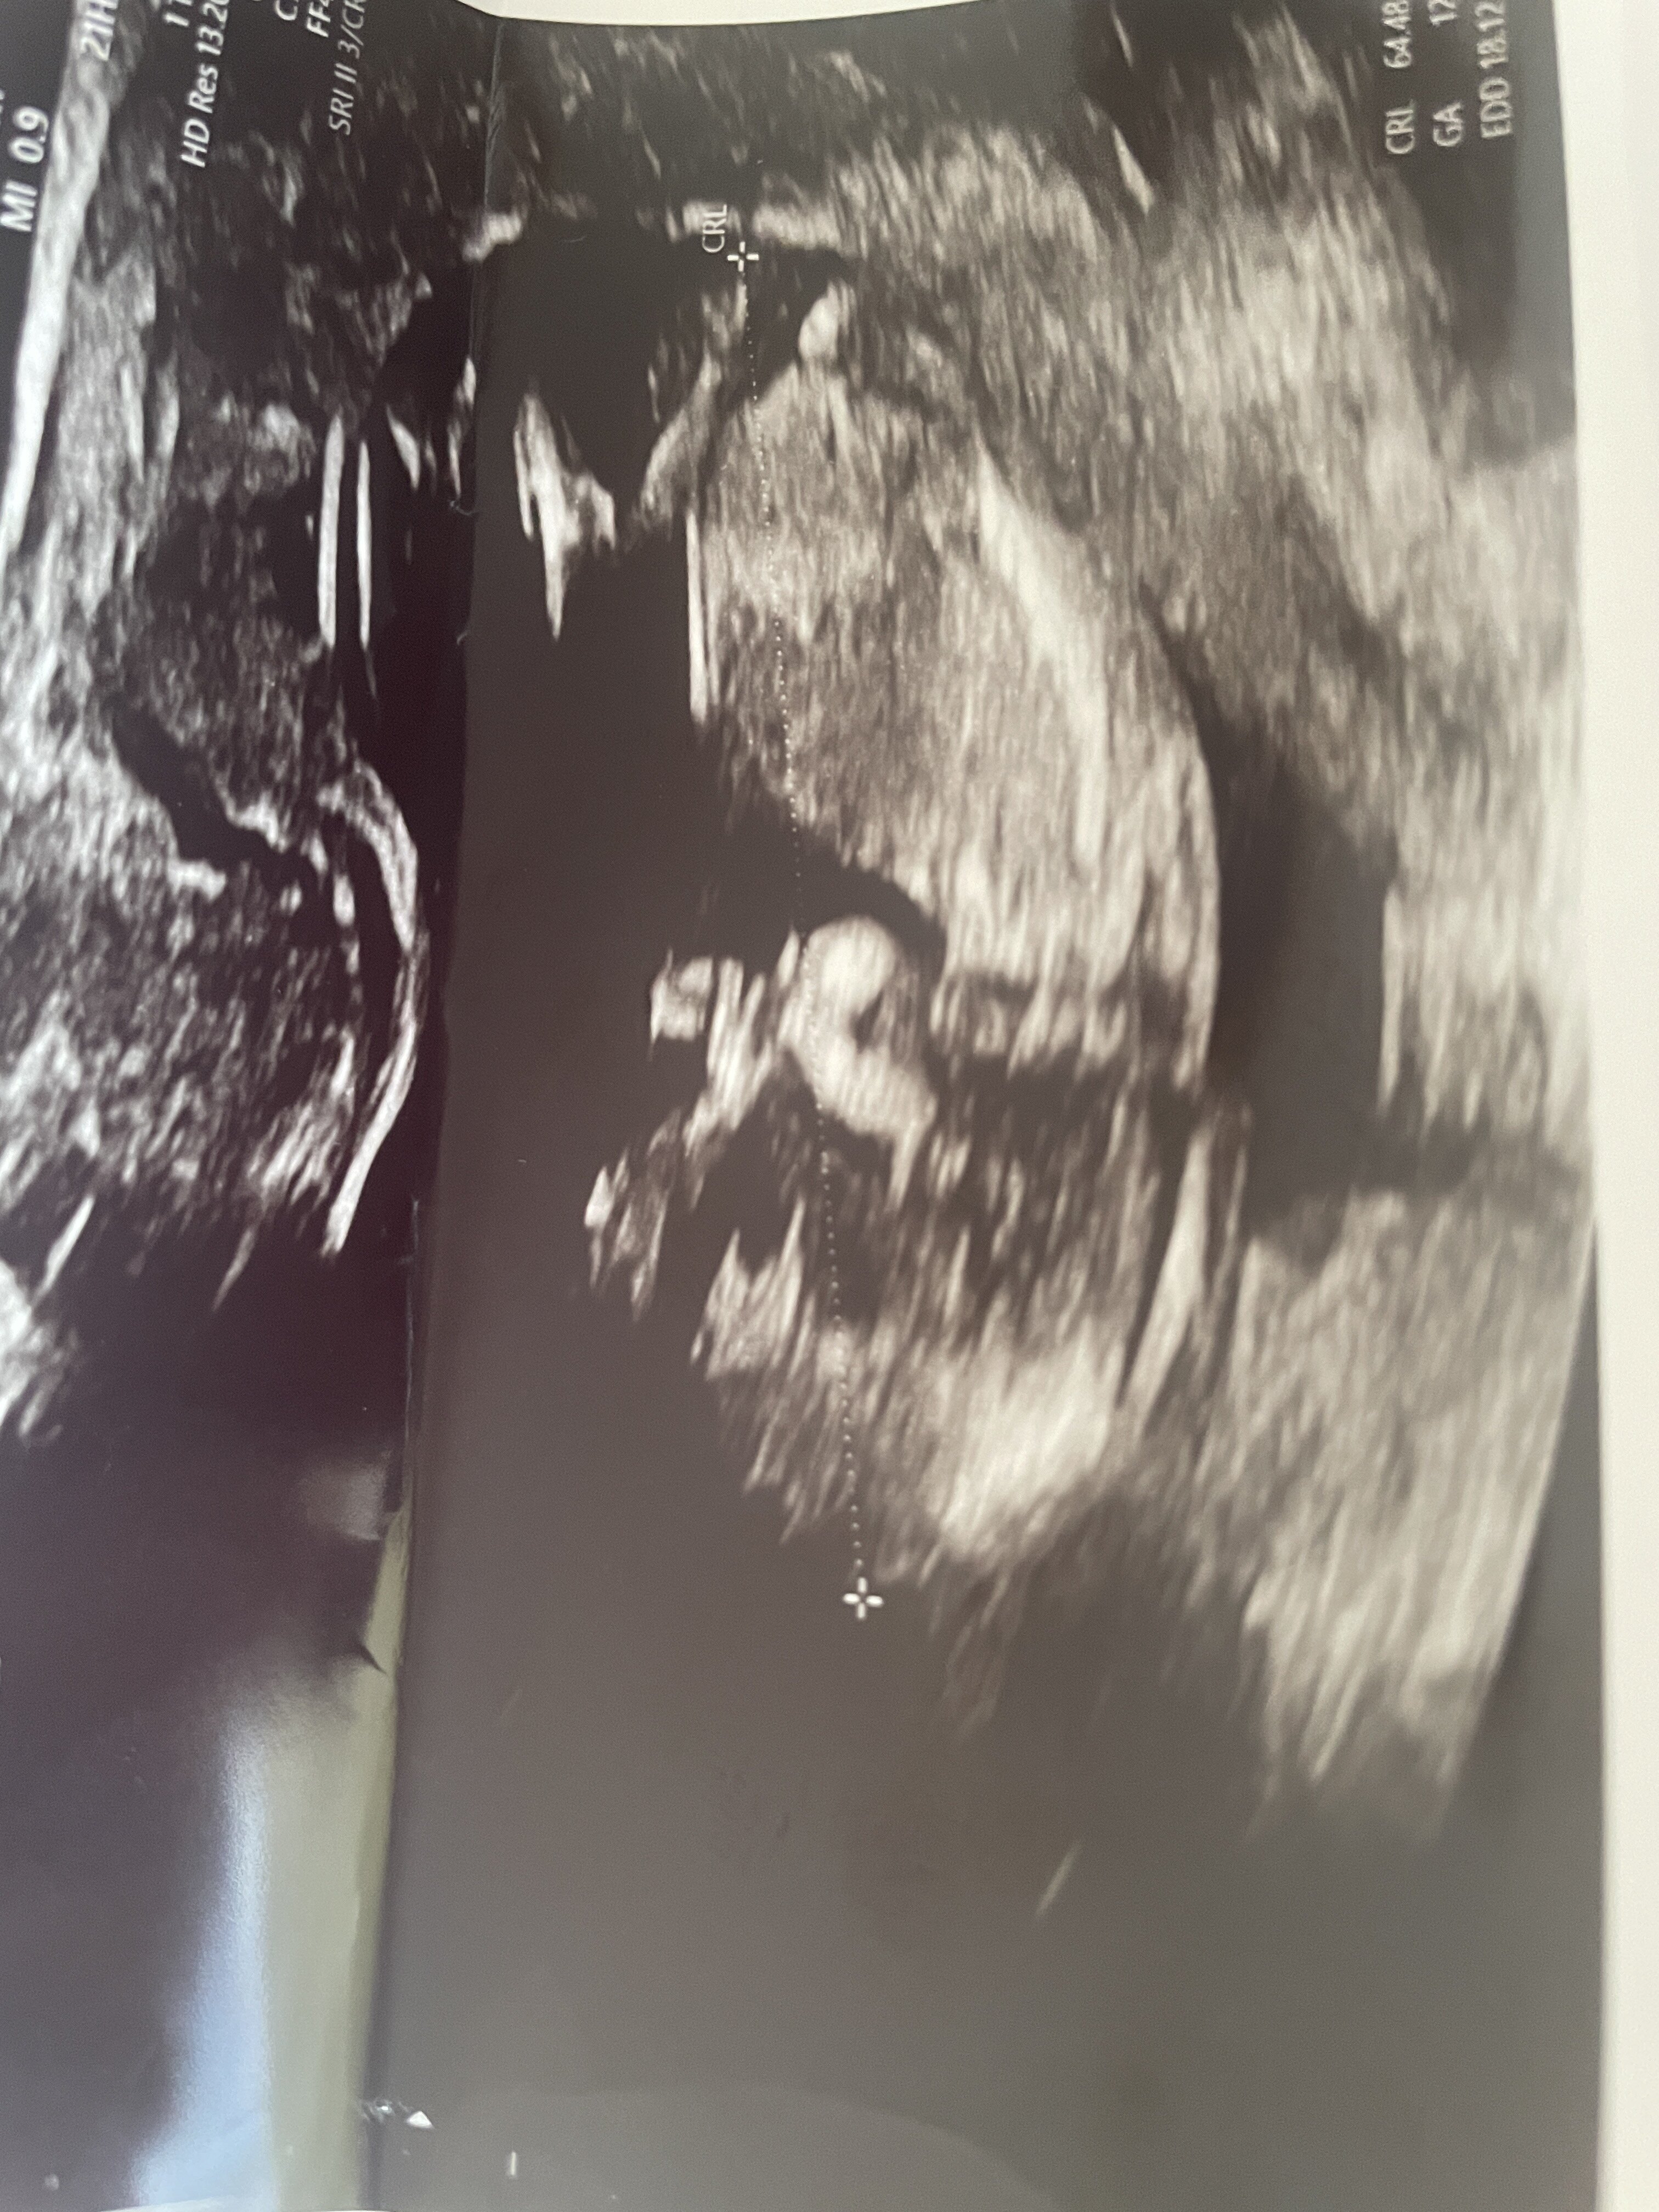

Witam mamy :)

Zwracam się z pytaniem czy umiecie wskazać płeć dziecka na podstawie zdjęcia USG? Jestem w 13 tygodniu :)

Takie „widełki” to na 70-80% dziewczynka, ale trzeba jeszcze poczekać, bo różnie to bywa jak się z wyrostka płciowego wykształcają docelowe narządy płciowe :)

No właśnie na prenatalnym gin powiedział że 60% chłopiec ale podświadomie czuje że to dziewczynka :) dziękuje za odpowiedź :)

Lekarz widzi więcej na usg niż tutaj z jednego zdjęcia, więc ciężko stwierdzić :) Ogólnie ta ocena wyrostków na tym etapie to trochę wróżenie z fusów. U syna się nie sprawdziło, u córki już tak :)